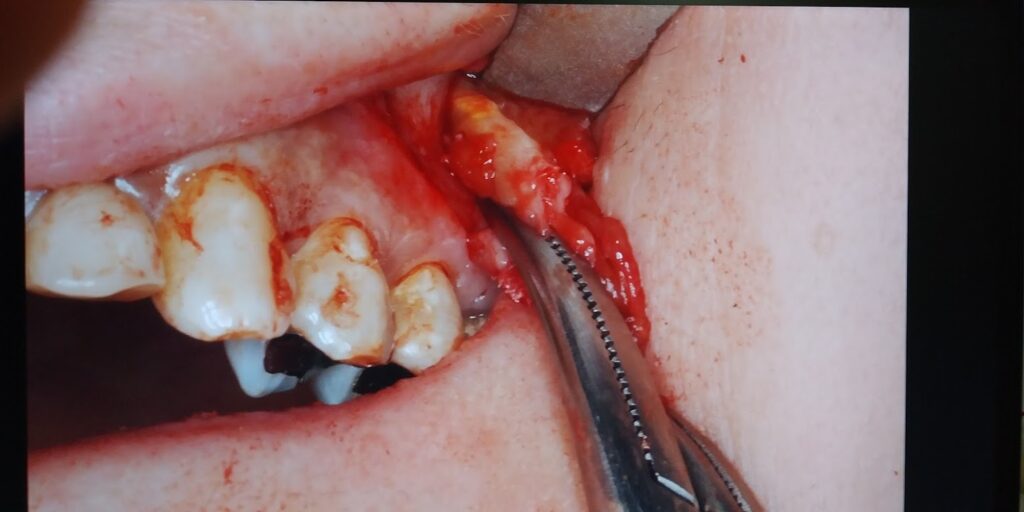

摘出部:上顎洞前壁の菲薄化している骨を開窓して上顎洞内の嚢胞を可及的に一塊で摘出し、左側上顎6の歯根端切除術を実施しました。

左側上顎6の歯根は経上顎洞的に頬側根 口蓋根を切除しました。上顎洞内の嚢胞と嚢胞内の歯科材料異物は摘出されています。(術中CT)